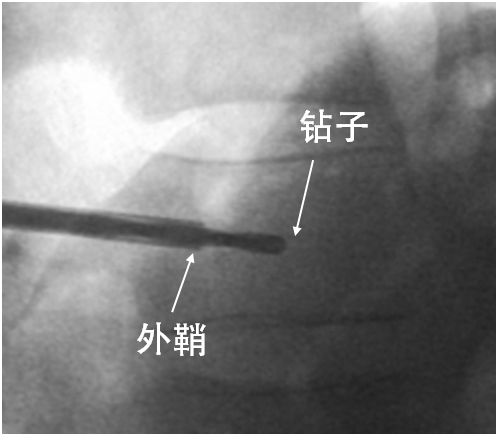

建立球囊通道

使用钻子开通道。

侧位相钻子直至椎体前中1/2交界处,正位钻头尖位于椎弓根影与棘突连线中点。

钻子必须出外鞘前端2cm,保证球囊完全进入椎体。

侧位像钻头尖在距椎体前缘2mm处停止正位显示钻头尖位于棘突边缘。